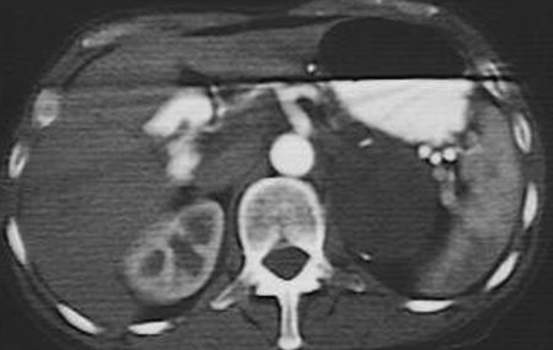

Интраренальная лоханка: рентгеновские снимки и примеры

Раздел: Фотоэссе